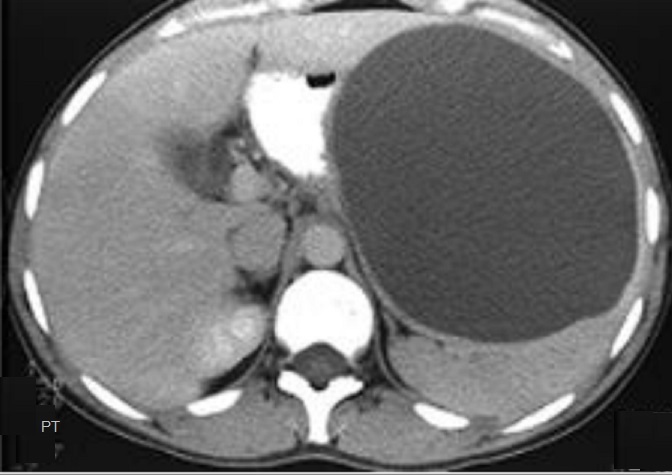

Image radiologique TDM une

splenomegalie par infection mononucleose . La rate

est volumineuse , tres epais , sa diamètre

antero-posterieure depasse plus de 10,5cm |

Image radiologique TDM en coupe

axial du splenomegalie d'une cirrhose du foie . La

rate est volumineuse ,a isodense , sa diametre

anterieuse - posterieuse depasse 11cm ,systeme veine

splenique est distendue . Le foie droit est a bord

crenele , reduction de volume , systeme veine porte

est distendue et en presence de l'ascite peritoneale |